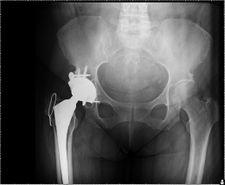

73y female presented with a periprosthetic fracture after sustaining a fall

Treated by ORIF of periprosthetic fracture of the right proximal femur around THR stem.

Protected weight bearing for 3 months